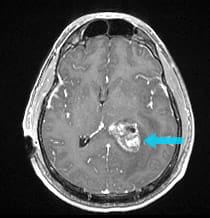

A 47-year-old man was suffering from relentless headaches, confusion, and visual disturbances. An MRI showed a large intraventricular tumor.

Pre-surgical scan shows a intraventricular tumor. Post-surgical scan shows the ventricle is visible on the scan as a dark space.

Pre-surgical scan shows a 2-inch intraventricular tumor.

The intraventricular tumor was nearly two inches in diameter. Because of its large size, the tumor was removed by two operations on two separate days using the Neuroendoport technique. The pathology report showed a subependymoma, a benign tumor in the ventricle. Surgical removal was achieved with minimal manipulation of the surrounding brain, allowing the patient's speech and vision function to be maximally preserved.